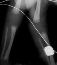

Hips were placed in traction for 2 weeks full time, and 6 weeks part-time( 12hr/day). The right hip failed traction: than had an open reduction and varus osteotomy at 1 year of age.

RESULT: ROM: R. knee 0-110 degrees, L. knee 0-120 degrees.; he started

ambulating 18 months with a well reduced femoral head

.